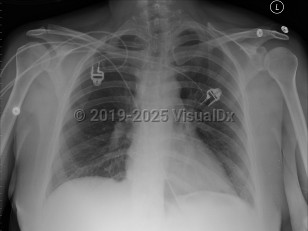

Chest pain, Dyspnea, 50-59 year old Female

Pericardial effusionPericardial effusion

Pulmonary edema